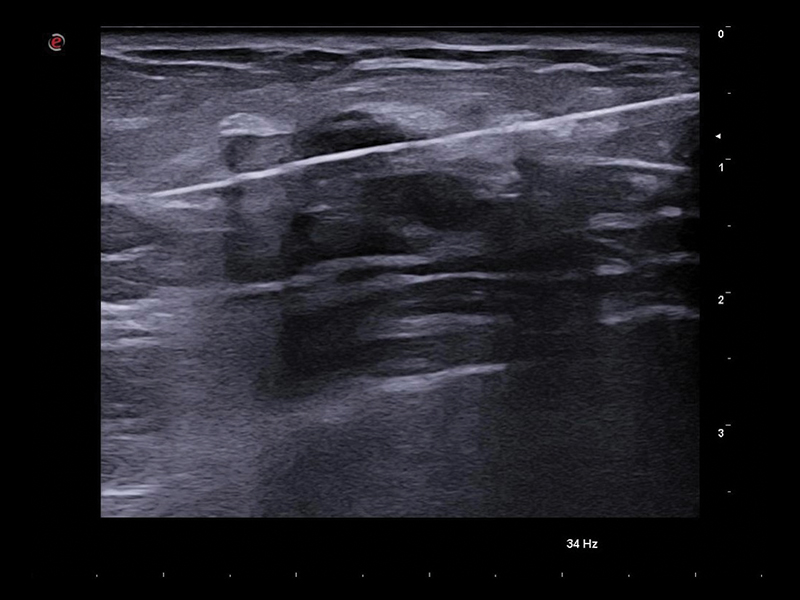

Clinical Images

Breast clinical image